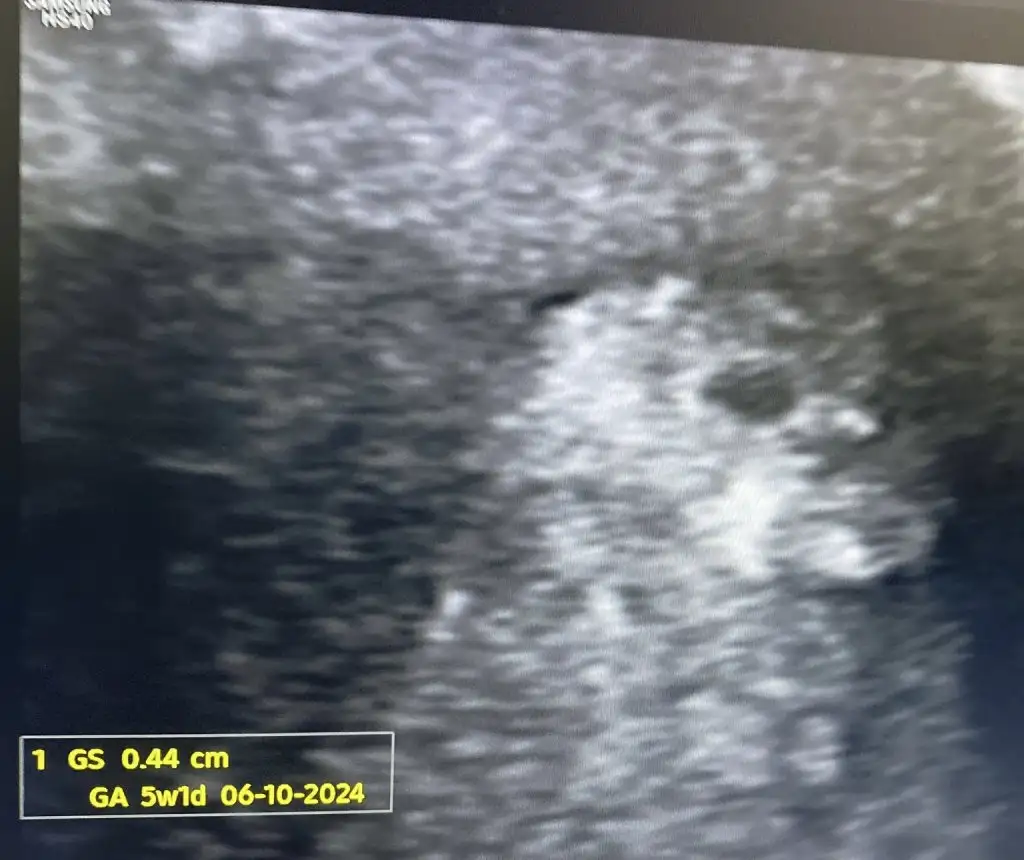

10.ayın 6 sına doğum tarihi olarak yazmışlar sanırım .inşaAllah o zamanlara gelebilirizkızlar baktıkça gülüyorum.Keseyi gördüğüm günkü fotoğrafta rahmim profil resmime benzemiyor muNe kadar kötü bir ultrason görüntüsü ya.Sizinki de böyle mi? 5+1 de

Amin bundan birşey seçilmiyor. İnternette de hiç bu kadar kötü görüntü görmedim10.ayın 6 sına doğum tarihi olarak yazmışlar sanırım .inşaAllah o zamanlara gelebilirizbir dahaki ultrasonda daha netleşir öper durursun inşaAllah

Normal canım y’a sıkıntı yapma 5+1 çok küçük nokta misali 1 kaç hafta sonra küçük bir insan şeklini bile alacak Allahın izniyle merak etmeAmin bundan birşey seçilmiyor. İnternette de hiç bu kadar kötü görüntü görmedim

kızlar baktıkça gülüyorum.Keseyi gördüğüm günkü fotoğrafta rahmim profil resmime benzemiyor muNe kadar kötü bir ultrason görüntüsü ya.Sizinki de böyle mi? 5+1 de